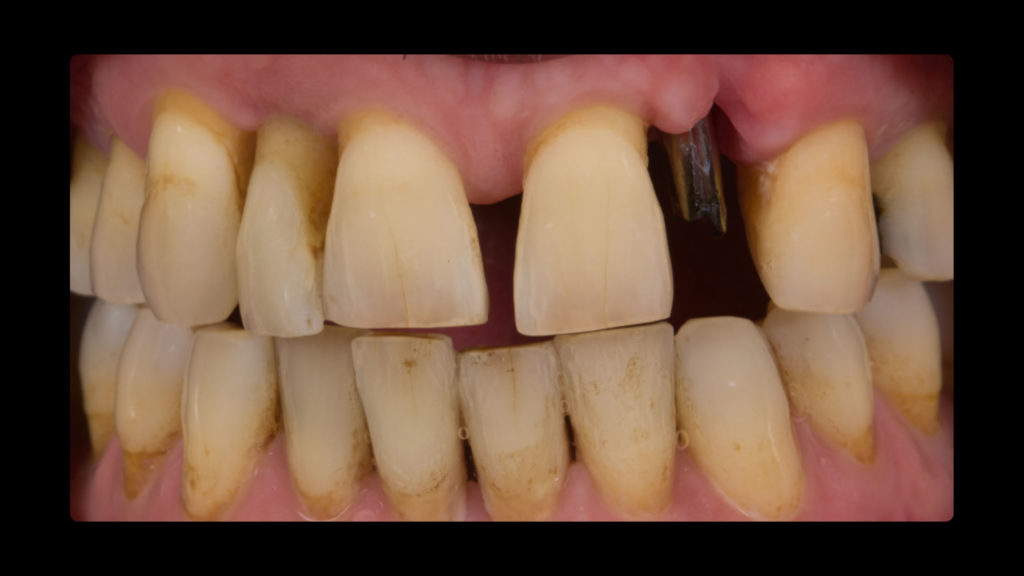

Klinische Phase

Bei dem Patienten handelte es sich um einen 49-jährigen Mann, Raucher (mehr als eine Packung pro Tag), mit einer Parodontalerkrankung, die vor drei Jahren diagnostiziert und behandelt worden war. Er wurde wegen des plötzlichen Verlusts seines Zahns 25 in der Klinik vorstellig. Im Rahmen der Untersuchung wurde zudem ein Mobilitätsgrad 3 an Zahn 22, aber auch an Zahn 12 konstatiert. Um den fehlenden Zahn 25 zu ersetzen, wurde ein Implantat in Betracht gezogen. Im Verlauf der weiteren klinischen Untersuchung wurden harte und weiche Konkremente und drei Amalgamfüllungen festgestellt. Ein näheres Screening und die Sondierung ergaben, dass weder Parodontaltaschen noch eine aktive Parodontalerkrankung vorlagen. Der Patient wurde über seine Situation informiert und eine Panoramaröntgenaufnahme angefertigt (siehe Abb. 1). Um zusätzlich zu prüfen, ob eine Implantation risikofrei durchführbar wäre und wie es um die Prognose bestellt sein würde, war auch eine DVT indiziert. Zudem wurde der Patient über die Risiken des Rauchens und die damit verbundenen möglichen Komplikationen sowie den Status der Parodontalanamnese aufgeklärt. Die Panoramaröntgenaufnahme zeigt die Merkmale einer älteren parodontalen Vorerkrankung. Die Alveole des Zahns 22 wies keinen Kontakt zum Knochen und Zahn 12 nur noch Knochen um den Apex herum auf (Abb. 1). Bei der Auswertung der DVT-Aufnahme wurde hinsichtlich der Länge und Breite ein gutes Knochenangebot für eine Implantation festgestellt, sodass der Zahn 22 extrahiert und in dieser Region implantiert werden konnte. Es wurde daher beschlossen, neben dem Zahn 25 – wegen dessen Verlusts der Patient die Praxis ursprünglich konsultiert hatte – auch den Zahn 22 implantatprothetisch zu rekonstruieren. Die prothetische Herausforderung im ästhetisch sichtbaren Bereich ist der Grund dafür, in diesem Artikel lediglich die Versorgung des Implantats in regio 22 zu beschreiben. Inseriert werden sollte dort ein Sweden & Martina Premium One-Implantat mit einem Durchmesser von 4,25 und einer Länge von 11,5 mm. Für ein bestmögliches Implantationsergebnis wurde das Implantat sofort nach der Extraktion des hochmobilen und als nicht erhaltungswürdig eingestuften Zahns 22 inseriert. Die Vorteile der Sofortimplantation wurden erstmals von Prof. Dr. Willi Schulte von der Universität Tübingen beschrieben. Der verbliebene Raum zwischen der Extraktionsalveole und dem Implantat wurde mit einer anorganischen porcinen Knochenmineral-Matrix (MinerOss XP, Camlog) mit dem Volumen 0,5 aufgefüllt. In der Abbildung 2 ist die Situation nach Insertion des Schweden & Martina Premium One-Implantats dargestellt. Nach vier Monaten Einheilzeit waren die Gewebe bereit und der Patient konnte definitiv versorgt werden.